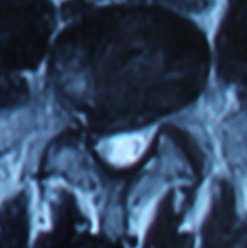

2. 患者董某,女,70岁,因“腰部疼痛并右下肢疼痛、麻木1年余,加重10天”入院。入院前曾多次行针灸、理疗、骶管封闭等治疗,经治疗后病情复发。入院见患者腰痛并右下肢疼痛,双足麻木,间歇性跛行,跛行距离约50米。查:直腿抬高试验右30°阳性,右踇背伸肌力、腓骨长短肌肌力Ⅲ级,双小腿外侧、足背皮肤感觉减退,右侧为甚。入院后诊断为腰椎间盘突出症。患者既往患高血压、冠心病、慢性胆囊炎、胆结石病史,形体肥胖。入院后完善检查,明确诊断,请相关科室会诊后认为手术风险大且患者形体肥胖,为手术增加难度,势必延长手术时间,增加手术风险。经科室讨论后行经皮椎间孔镜下髓核摘除,手术麻醉方式为局麻。入院后第三日手术,经椎间孔入路椎间孔镜下髓核摘除椎管扩大成形术。手术顺利,术中无出血,手术时间约1小时。术中可与患者交流。术后患者即可感右下肢无疼痛,第二天佩戴腰围下地活动后双下肢无不适。术后第三天出院,术后第三天复查腰椎MRI示突出髓核已摘除,神经根无受压。术后随访三月,患者目前病情恢复良好,无下肢疼痛。

术后第三天腰椎MRI